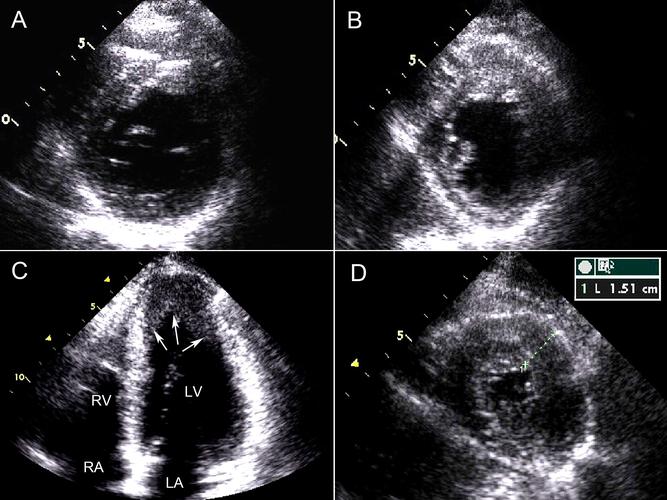

肥厚型心肌病超声图片,肥厚型心肌病心电图

【病例帮】化学消融,这例肥厚型梗阻性心肌病你会如何

第2节 肥厚型心肌病

肥厚型心肌病?梗阻还是非梗阻?

【原创】肥厚性非梗阻型心肌病

肥厚型心肌病sam征图片